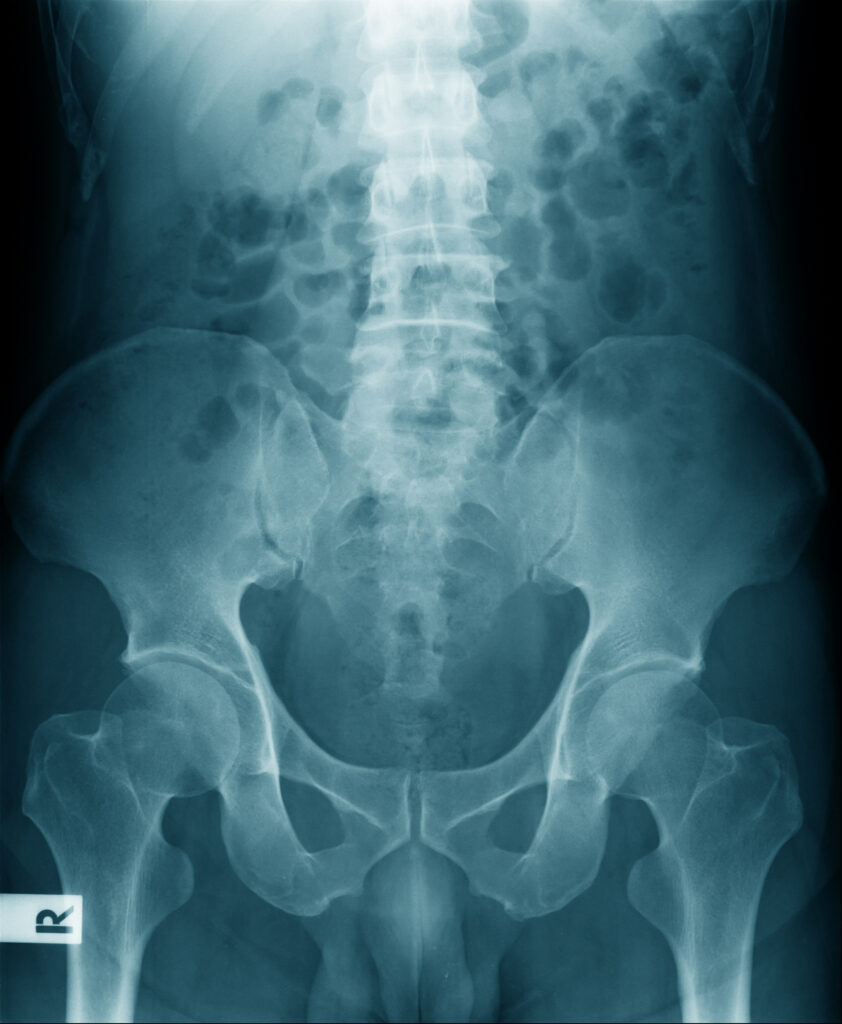

hip dysfunction and social security disability benefits